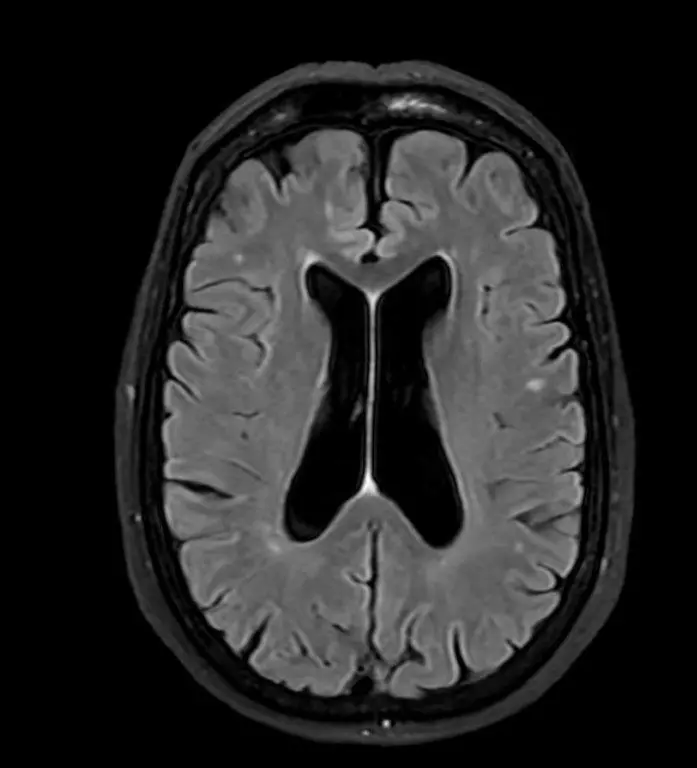

Hvad er en MR-scanning af hjernen?

En MR-scanning af hjernen er en avanceret billedteknik, der bruger magnetfelter og radiobølger til at skabe detaljerede billeder af hjernens strukturer. Metoden har været brugt siden 1980’erne og er i dag det foretrukne værktøj til at opdage forandringer og forhindre alvorlige konsekvenser.

Ved en MR-scanning tages omkring 2.000 detaljerede billeder, som giver et præcist indblik i hjernens anatomi, herunder:

- Hjernestammen og cerebrospinalvæsken, der omgiver hjernen og rygmarven

- Hjernebarken (den grå substans), som styrer kroppens funktioner

- Den hvide substans med nervebaner, der forbinder hjernens forskellige dele

Hvilke neurologiske sygdomme kan opdages?

En MR-scanning af hjernen er den bedste metode til at diagnosticere en række tilstande som:

– Godartede og ondartede tumorer (hjernesvulster)

– Kræftspredning til hjernen (metastaser)

– Blodpropper og blødninger i hjernen

– Inflammatoriske tilstande

– Multipel sklerose

– Epilepsi

– Alzheimers sygdom

– Skader efter hovedtraumer

Eksempler på MR-scanninger